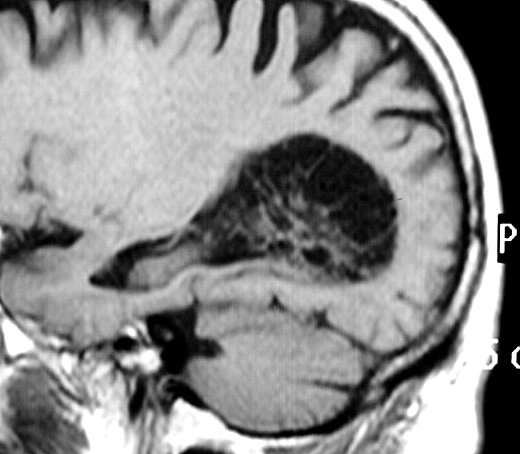

ГМ. Субэпендимома 2. +

Субэпендимома